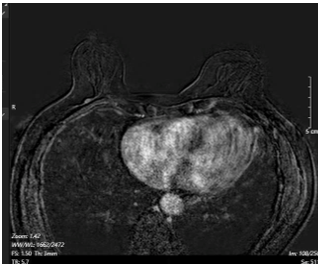

- Cộng hưởng từ tuyến vú có tiêm tương phản: Hình ảnh đám ngấm thuốc trung tâm vú phải, không tạo thành khối, dài 43mm, vùng tổn thương 15x15mm, trung tâm tổn thương dưới núm vú 22mm, nhưng tổn thương ngấm thuốc tới tận núm vú, núm vú ngấm thuốc mạnh (BIRADS 6). Tổn thương chưa xâm lấn cơ thành ngực. Hạch trong nhu mô vú phải vị trí 8h, cách núm vú 6cm, kích thước 4x6mm,ngấm thuốc từ từ tăng dần. Không thấy bất thương vú trái (BIRADS 1).

Hình 3:

Hình ảnh cộng hưởng từ tuyến vú có tiêm tương phản. Hình ảnh đám ngấm thuốc trung tâm vú phải đã lan tới núm vú (BIRADS 6) (mũi tên màu xanh dương).

Hình 4: Hình ảnh cộng hưởng từ tuyến vú có tiêm tương phản. Hình ảnh Hạch trong nhu mô vú phải vị trí 8h (BIRADS 3) (mũi tên màu xanh lá).